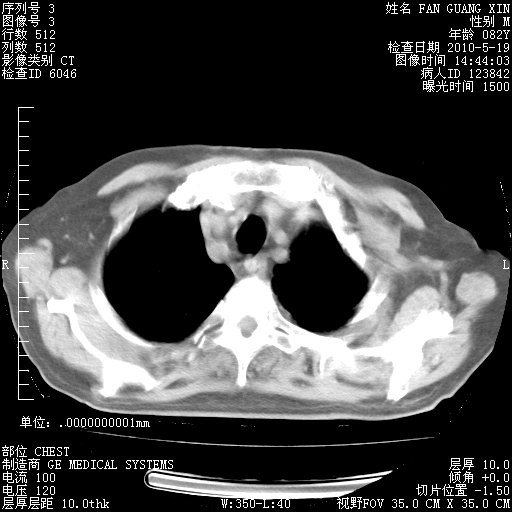

复查肺部CT,明显好转。为什么发热呢?

治疗3周后的肺部CT